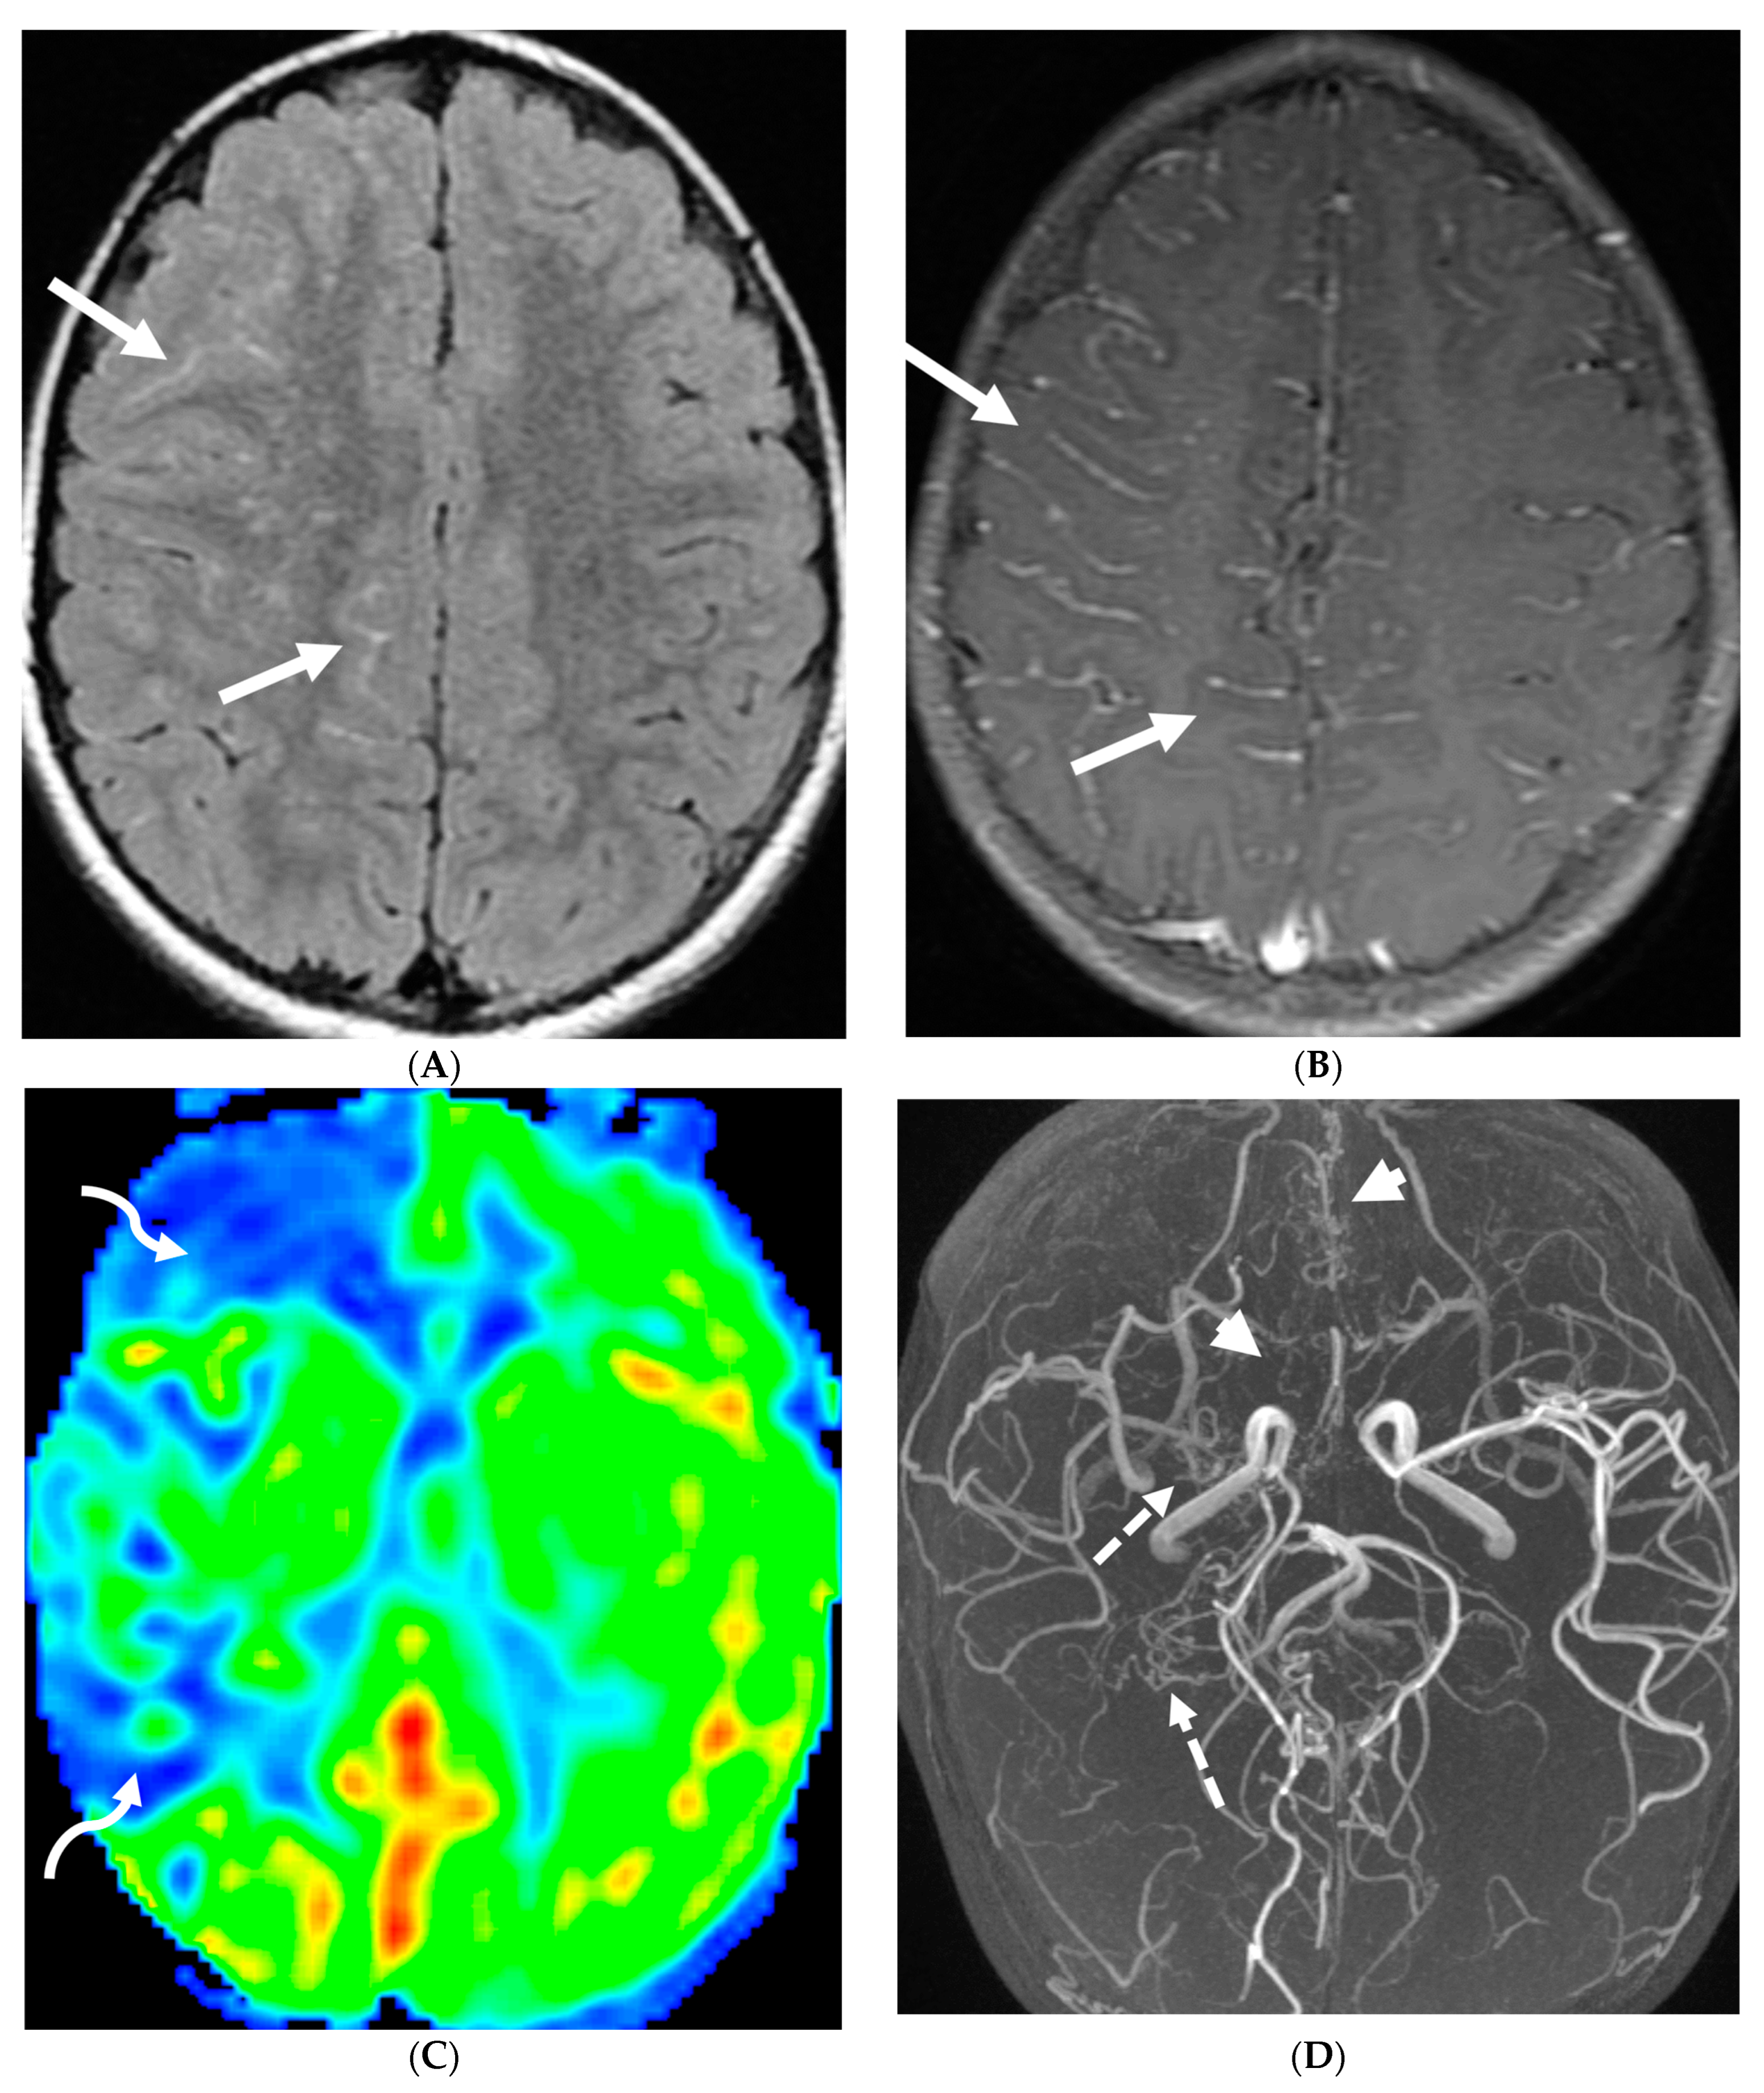

In children with moya moya, the LME is termed the “ivy sign” as the appearance resembles creeping ivy (Figure 18) [93]. LME arises due to two key factors in MMD, namely neovascularization and retrograde flow from congested pial vessels [94].

Figure 18.

Axial FLAIR (A), MRA (B), axial ASL perfusion (C) and axial T1 post contrast (D): 7-year-old girl with Down’s syndrome: Abnormal FLAIR hyperintense signal with LME along the right cerebral convexity sulci, predominantly in the frontoparietal region representing “ivy sign” (arrows). Asymmetric decreased perfusion in the right frontal and temporal regions (curved arrows). The M1 segment of right MCA is not visualized with extensive moyamoya vessels (dashed arrows). The M2 and M3 branches of right MCA are asymmetrically attenuated. Bilateral A1 segments are not identified with extensive collateralization and diminutive caliber of A2 and A3 segments (arrow heads).

Although LME is a supportive feature in the diagnosis of moya moya, LME is a marker of collateral vessel status and less LME is a marker of severe clinical symptoms and poor postoperative outcomes [95]. In addition, degree of reduction of LME after surgery has been proposed to be a marker of effective surgery [96].